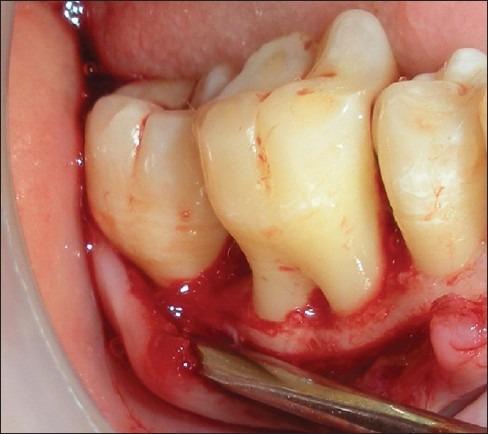

The present study was undertaken to evaluate the effectiveness of the combination of hydroxyapatite and β-tricalcium phosphate bone alloplast with bioresorbable guided tissue regeneration membrane for the treatment of mandibular grade II furcation defects.

A total of eight patients, four females and four males, in the age group of 18 to 65 years, with bilateral buccal grade II furcation defects in the mandibular molars, participated in the study.

The mean gain in the relative clinical attachment levels in the test and control groups, at the end of six months, were 2.50 and 1.63 mm, respectively. The mean change in the horizontal probing depth values at the end of six months in the test and control groups were 2.88 and 1.63 mm, respectively. The mean reduction in the vertical probing depth values in the test and control groups were 1.50 and 1.38 mm, respectively.

The resorbable GTR membrane with bone material was more effective than open debridement alone, in the treatment of furcation defects.